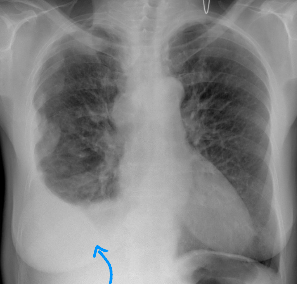

Rx toracică, incidență P-A

DESCRIERE:

DX: emfizem pulmonar

DD: